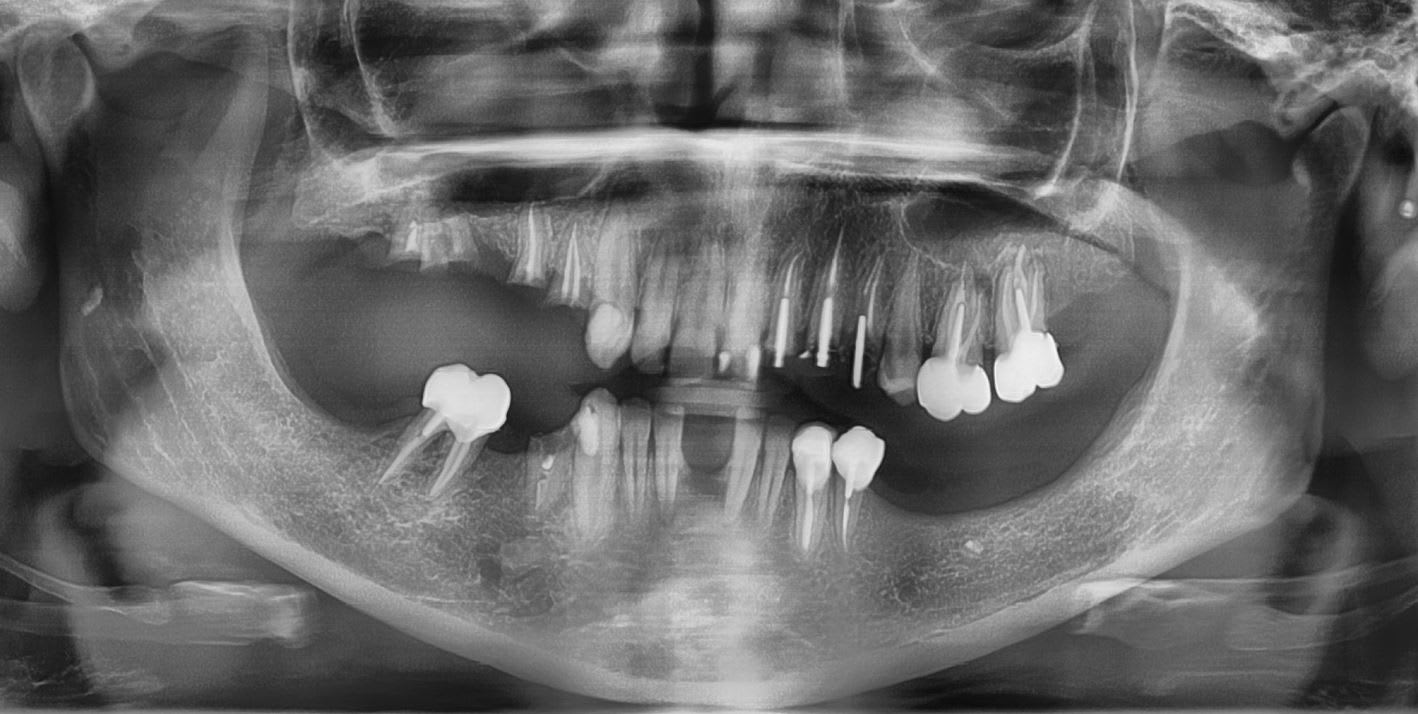

Mise_en_charge_immédiate_Positdental_R._004_zctmul.jpg

Mise_en_charge_immédiate_Positdental_R._005_b3jo3x.jpg

Mise_en_charge_immédiate_Positdental_R._006_ddh2n0.jpg

Mise_en_charge_immédiate_Positdental_R._001_hwwkac.jpg

Mise_en_charge_immédiate_Positdental_R._003_htglwg.jpg

Mise_en_charge_immédiate_Positdental_R._002_xkbebj.jpg